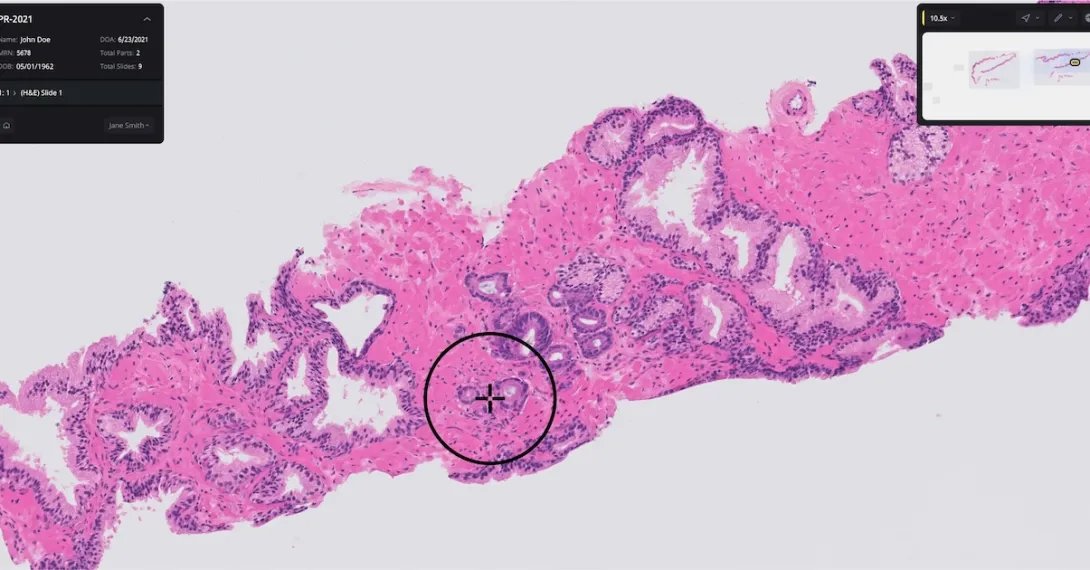

Paige, a digital pathology diagnostics company, has received De Novo marketing authorization from the Food and Drug Administration for its artificial intelligence software that helps detect prostate cancer.

The Paige Prostate software analyzes digitized biopsy slides and identifies areas that could be cancerous for the pathologist to review further.

Authorization for Paige Prostate was based on a clinical study where 16 pathologists examined 527 prostate biopsy slides. The software improved the pathologists’ ability to detect cancer on individual slide images by an average of 7.3% (from 89.5% to 96.8%).

Further, pathologists using Paige’s software had a 70% reduction in false-negative diagnoses and a 24% reduction in false-positive diagnoses. Paige Prostate also helped boost nonspecialist pathologists’ diagnostic accuracy to the same level as prostate specialists who were not using the software.

“Pathologists examine biopsies of tissue suspected for diseases, such as prostate cancer, every day. Identifying areas of concern on the biopsy image can help pathologists make a diagnosis that informs the appropriate treatment,” Dr. Tim Stenzel, director of the FDA’s Office of In Vitro Diagnostics and Radiological Health, said in a statement.